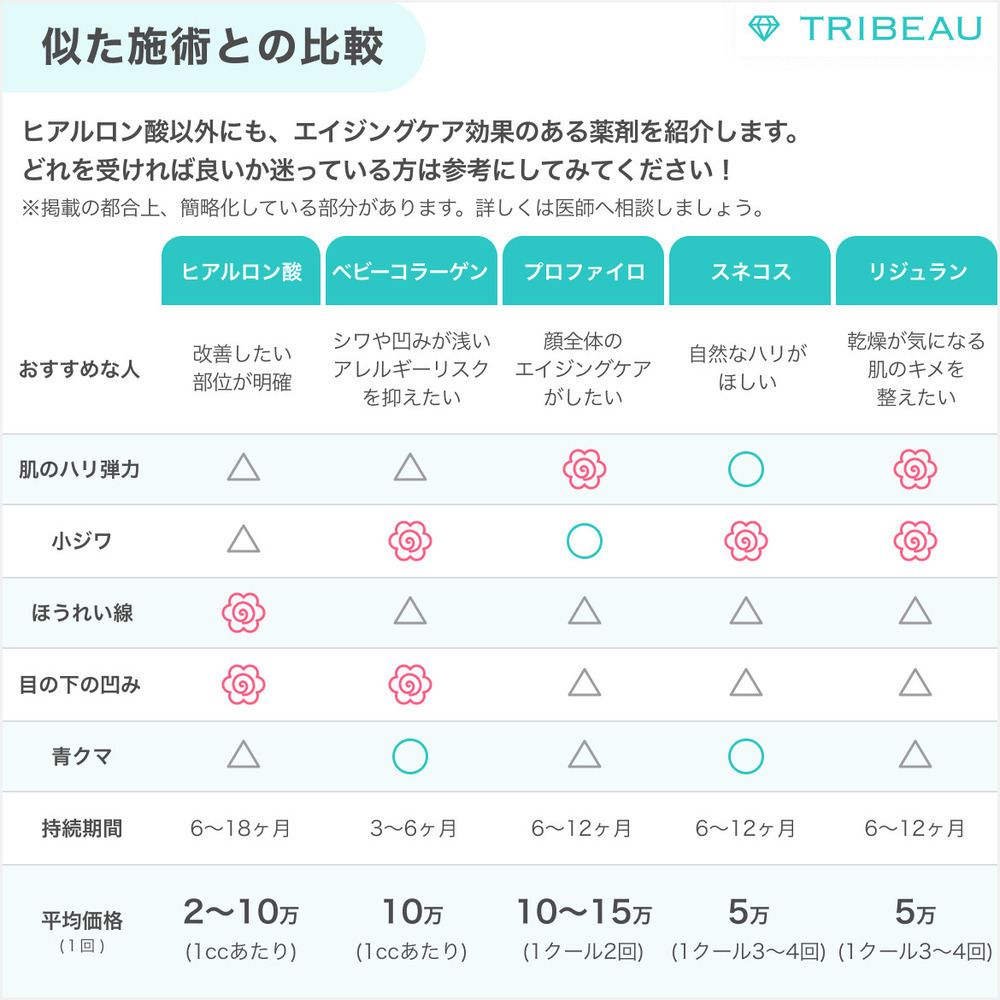

リスク・副作用

内出血腫れ赤みむくみ痛み感染塞栓